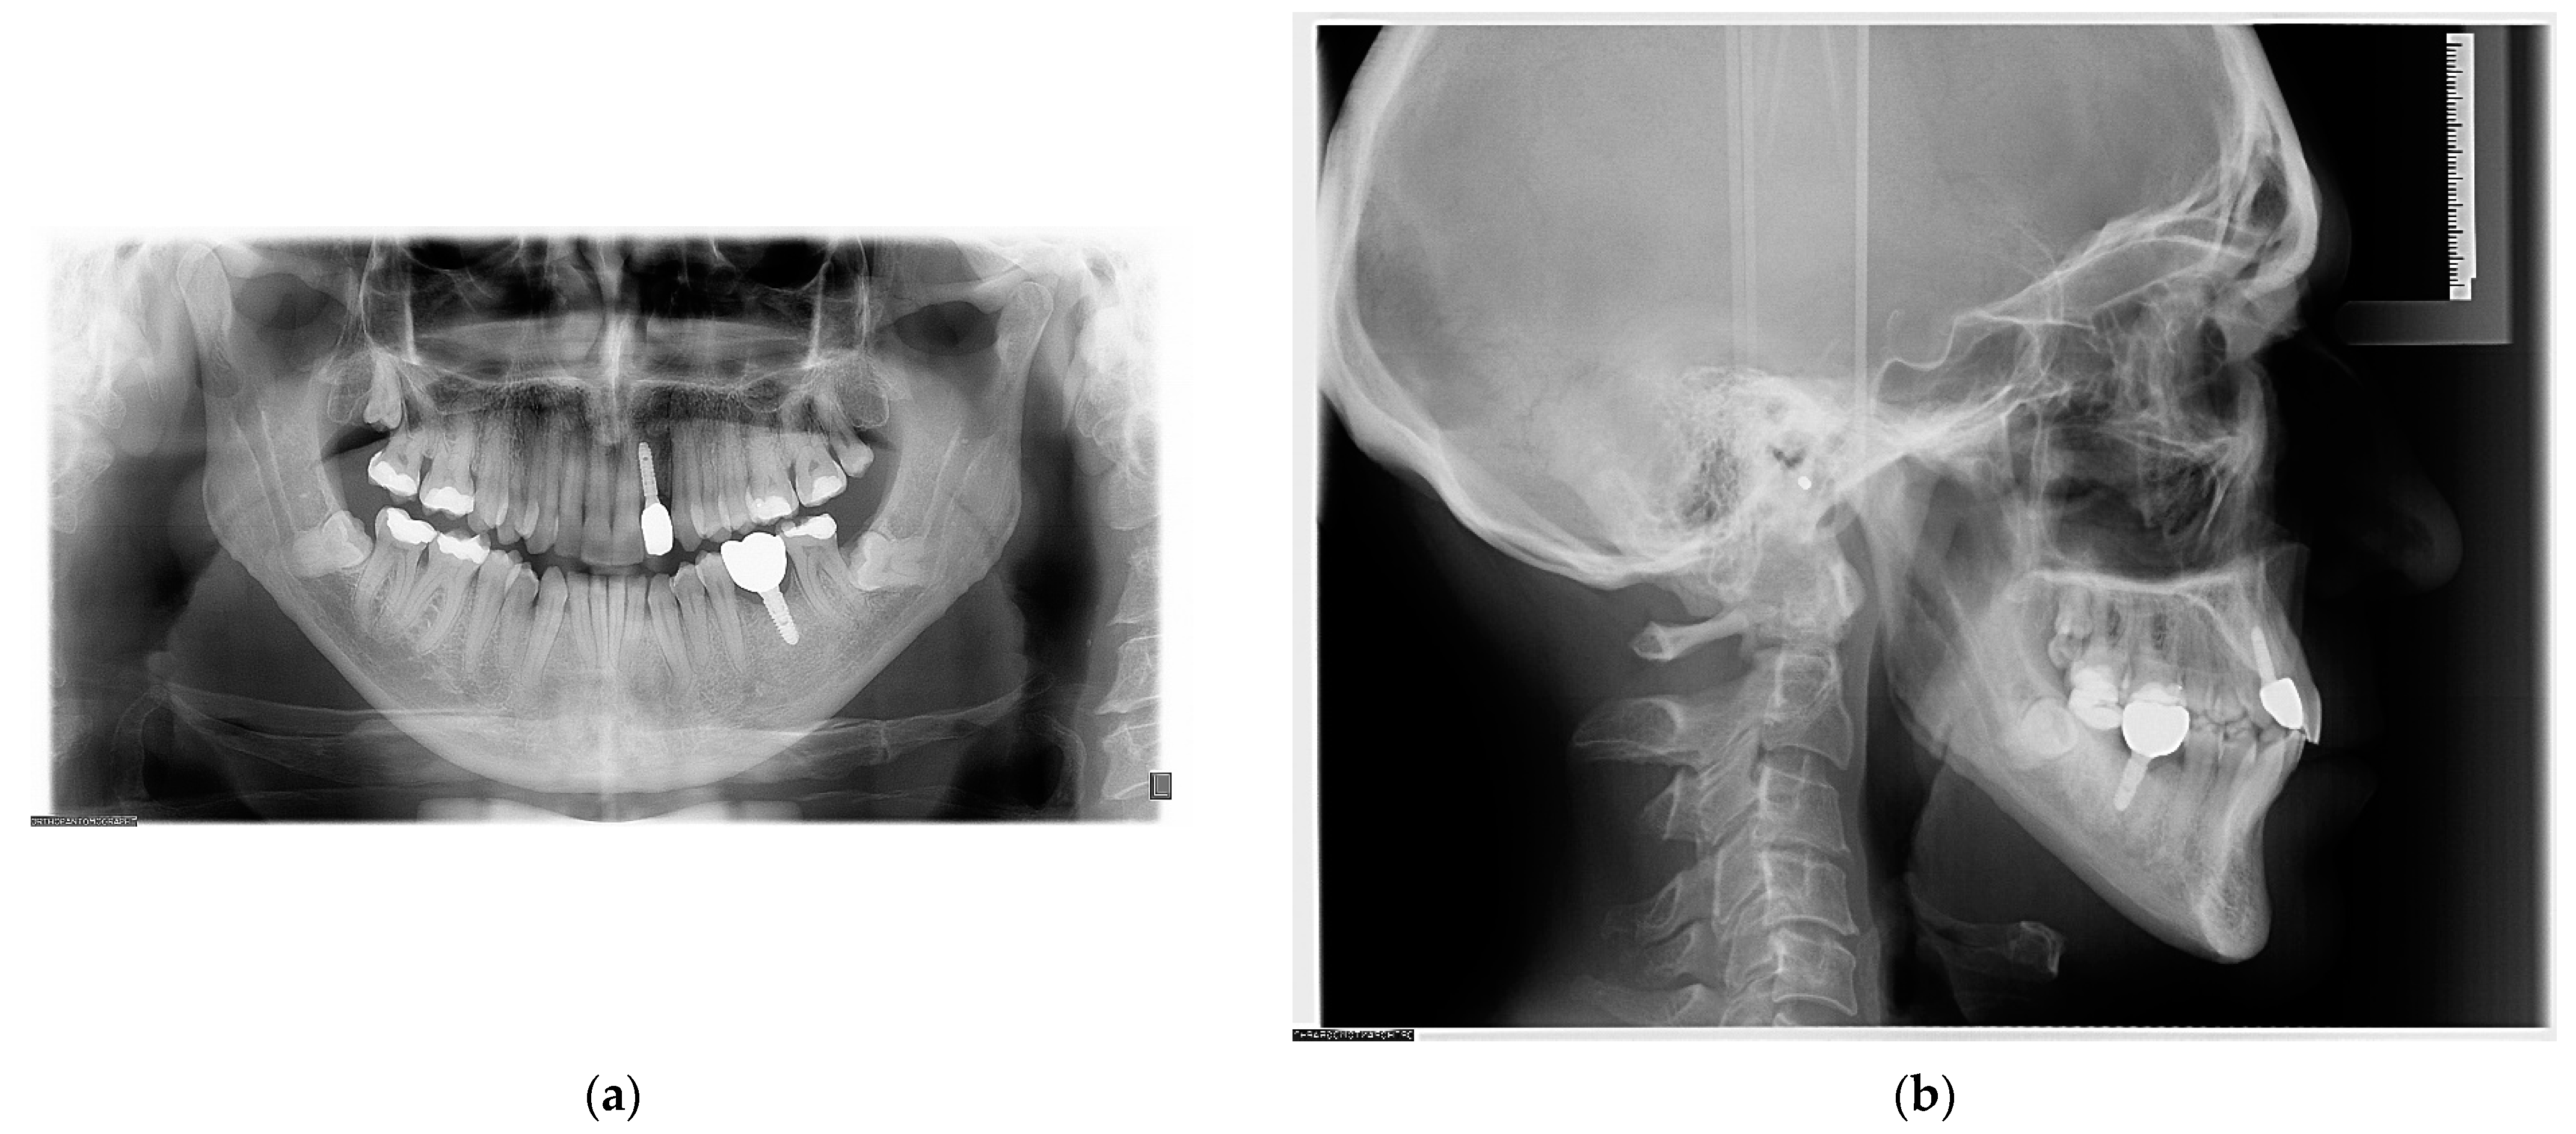

2. Case Report